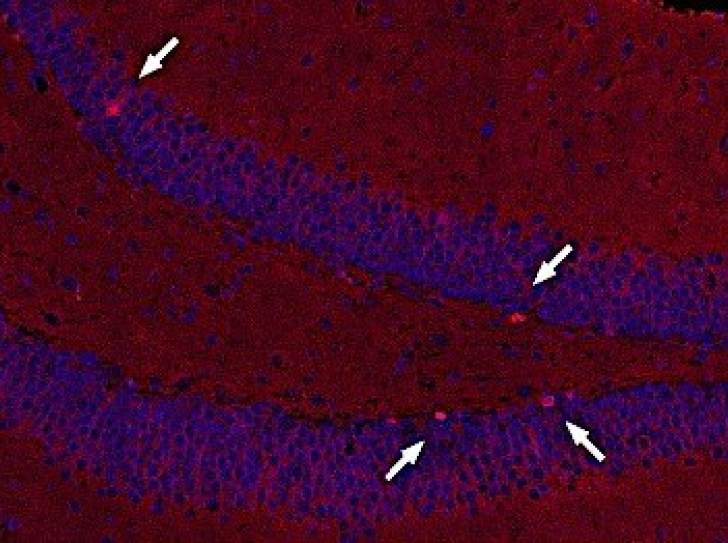

La dépression et l’efficacité des antidépresseurs dépendent de la composition du microbiote intestinal

Pas d’esprit sain sans un microbiote sain ? Une étude conjointe entre l’Institut Pasteur, le CNRS et l’Inserm démontre que la population bactérienne…